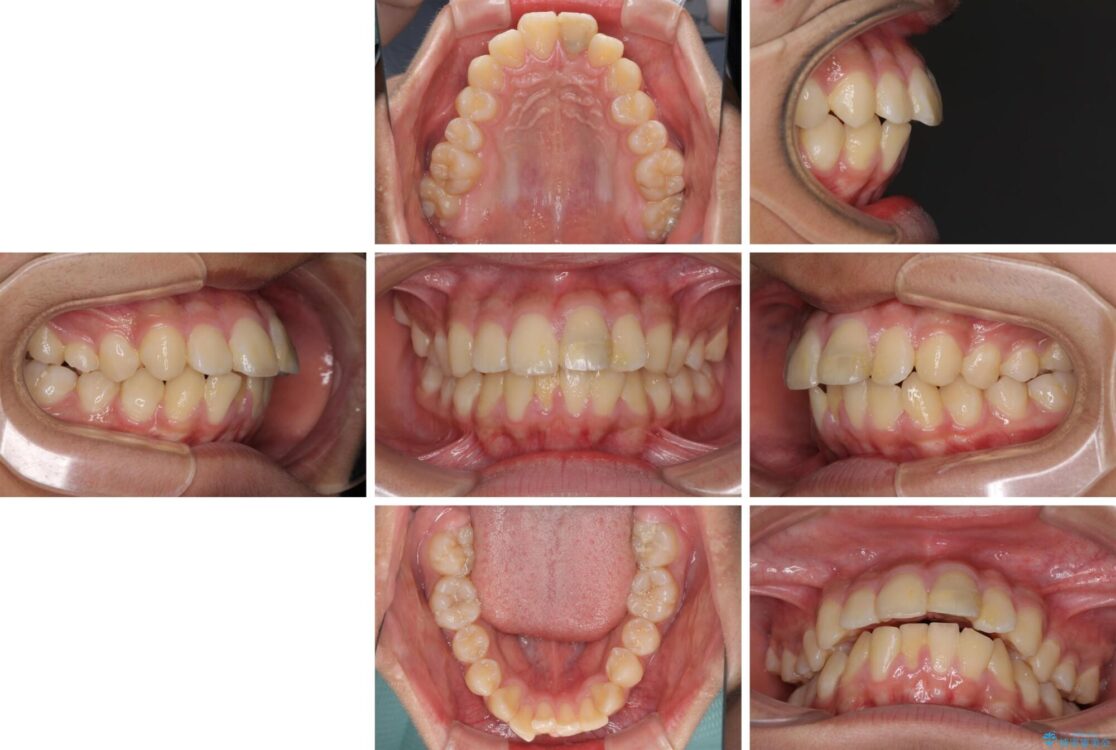

治療後

• 膨らんだ口元 ワイヤー装置での抜歯矯正 治療後画像